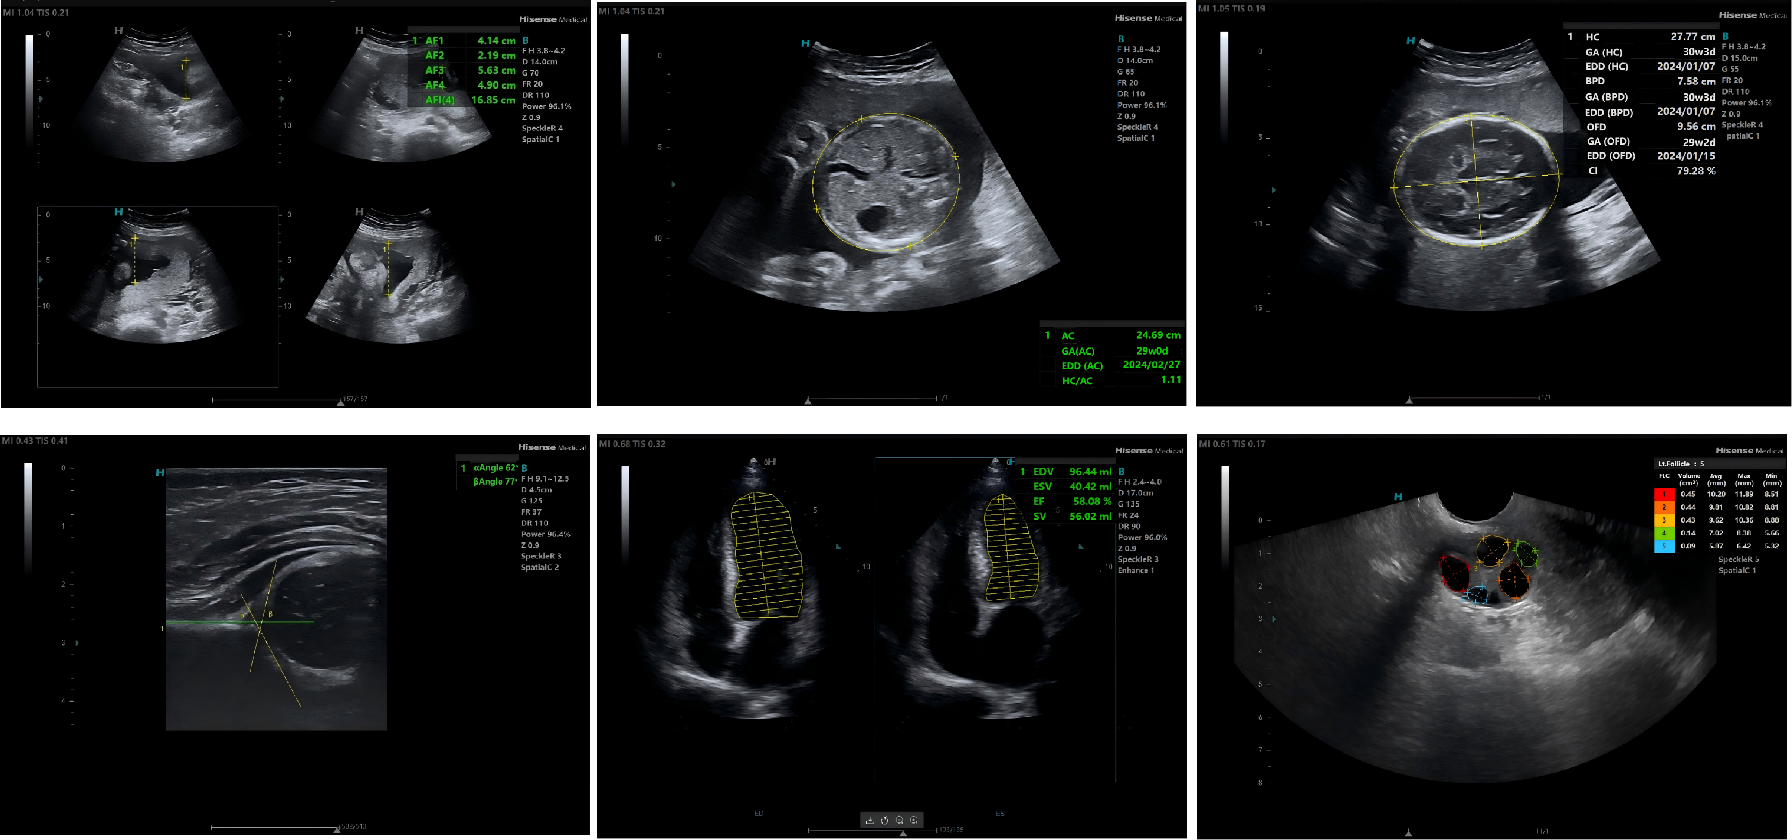

Intelligent Assistance, Precision Measurement

Smart Assisted Diagnosis and: Auto Measurement Functions of Key Parameters Enhance Diagnostic Efficiency .

Clinical Imaging

Continuous probe innovation ensures high-quality imaging across applications.